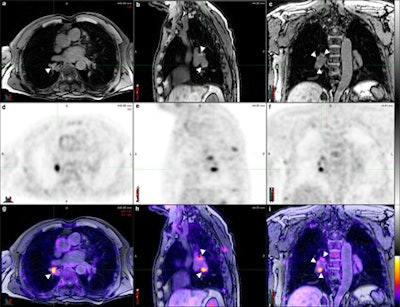

FDG-PET/MRI shows similar performance to FDG-PET/CT for lymph node staging in lung cancer, with "substantial" reader agreement in determining tumor staging, according to a study published online on June 14 in European Radiology.

Using a three-segment model for attenuation correction, PET/MRI for lymph node staging in lung cancer also showed a "strong parallel" to PET/CT relative to maximum standardized uptake values (SUVmax) and diagnostic performance. Lead study author is Dr. Andres Kohan from the department of radiology at University Hospitals Case Medical Center at Case Western Reserve University in Cleveland, Ohio, U.S.

Overall interobserver agreement was "high" (Κ = 0.86) for PET/CT and "substantial" (Κ = 0.70) for PET/MRI among the four readers, Kohan and colleagues described. They also found full agreement among readers on the nodal stage in nine (81%) of 11 PET/CT images and seven (63%) of 11 PET/MR images.

Comparing the results between PET/CT and PET/MRI for the four readers, the researches found disagreement on the N stage for five of 44 evaluations. Four of the five cases were rated with a higher N stage with PET/MR than with PET/CT, but the difference was not statistically significant, the researchers concluded.

PET with MRI-based attenuation correction for non-small cell lung cancer lymph node staging has a "very strong quantitative correlation to PET/CT, while it may be of a similar qualitative value," Kohan and colleagues concluded.

The results indicate that while interreader agreement is "almost perfect for PET/CT, it is still substantial in PET/MRI," they noted. "Nonetheless, we hypothesize this lower agreement was due to a learning curve in MRI interpretation, especially for nuclear medicine physicians, and the lack of other morphologic and multiparametric sequences in our PET/MRI protocol."

The potential advantage of using PET/MRI instead of PET/CT for lung cancer is not yet clear, but there may be some cases in which PET/MRI "may be superior, such as lymph node assessment," the researchers noted. "The current experience with PET/MRI in lung cancer is limited."